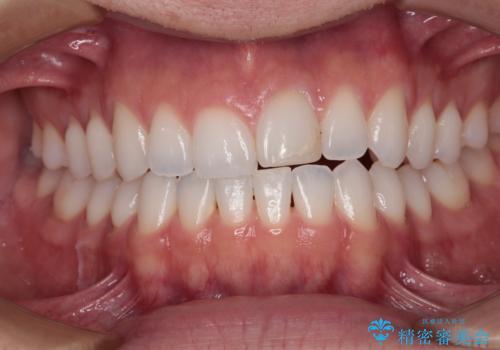

ぶつけて変色した前歯 オールセラミッククラウン治療

定期的にホワイトニングをされていることや、前歯の歯列が左右非対称であることから、色合いや形態の修正が多くなることが予想されたため、オーダーメイドタイプのグレードを選択していただき、治療を進めて行くこととしました。

予想通り色と形の修正が多く必要となりましたが、最終的には納得のいく仕上がりとなりました。